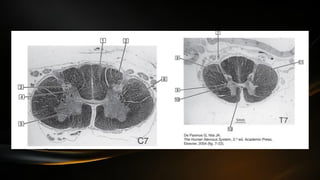

Estructura general

• La medula espinal posee en su centro sustancia gris y a la periferia le

rodea sustancia blanca

• La sustancia gris se observa en las secciones transversales en forma

de “H” o alas de mariposa, en el centro puede observarse la comisura

gris

• De manera que se asciende rostralmente se encontrara el cuarto

ventrículo a la altura del bulbo raquídeo

• El conducto central en la sustancia gris divide la comisura en dos

zonas: comisuras grises anterior y posterior

• Las astas anteriores es ancha e irregular; mientras que el asta

posterior es mas estrecha y se torna puntiaguda al llegar hasta el

surco posterolateral

• A nivel de T1 a L2 ocurre el aparecimiento del asta lateral

• A nivel del asta posterior puede encontrarse el tracto de Lissauer o

dorsolateral, el cual es un conjunto de axones cortos ascendentes y

descendentes que se desprende de las fibras radiculares posteriores

al entrar en la medula espinal

• Hay una variación de la forma de la sustancia gris conforme se

desciende en la medula espinal (a nivel de los miembros la sustancia

gris se torna mas gruesa)